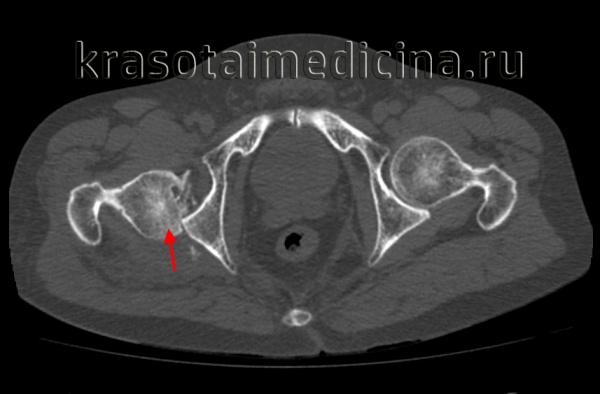

Диагностика вывихов бедра, как правило, не вызывает затруднений у врача-травматолога. Для уточнения положения головки бедренной кости и исключения возможных костных повреждений проводится рентгенологическое исследование в двух проекциях или МРТ тазобедренного сустава.

КТ таза. 3D-реконструкция. Красная стрелка – вывихнутая головка бедренной кости, синяя стрелка – «пустая» вертлужная впадина.